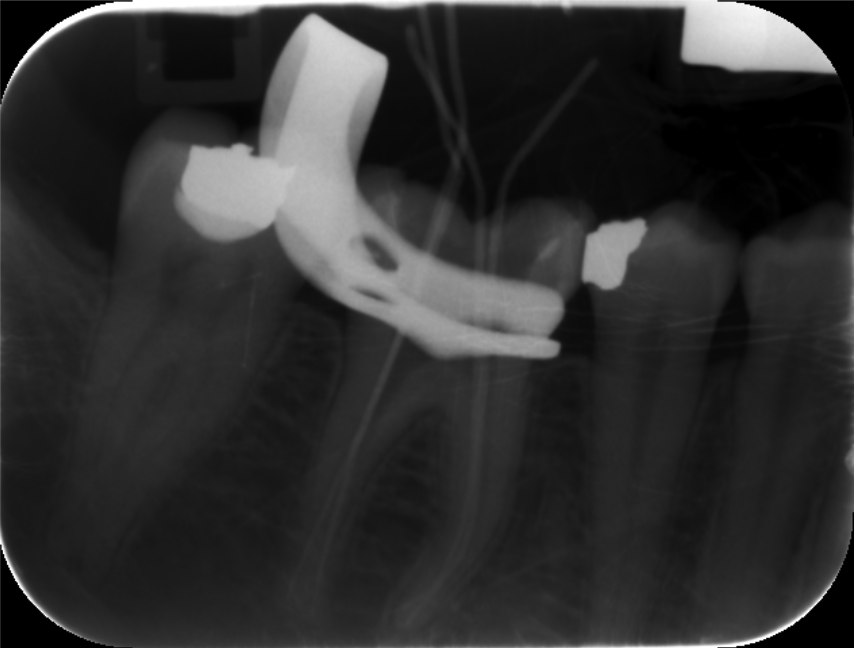

These included team building, communication, photography, endodontics, composite and amalgam restorations, oral surgery, prosthodontics and paediatric dentistry Through these courses I was able to improve on my knowledge and skills from university and implement them in my everyday practice. I have also been keeping a photographic record of my work throughout this year which allows me to reflect on what went well and what I can improve on in the future. space to display your timeline of professional development